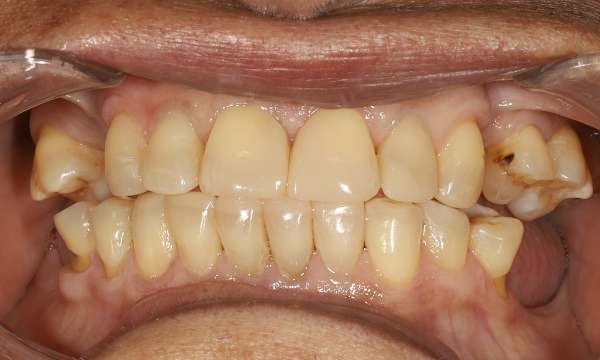

Composite Restorations

This case shows how composite restorations can be used to repair worn front teeth. By conservatively and strategically opening the bite, we were able to create a harmonious and balanced bite, ensuring the newly restored teeth are protected from excessive chewing forces.